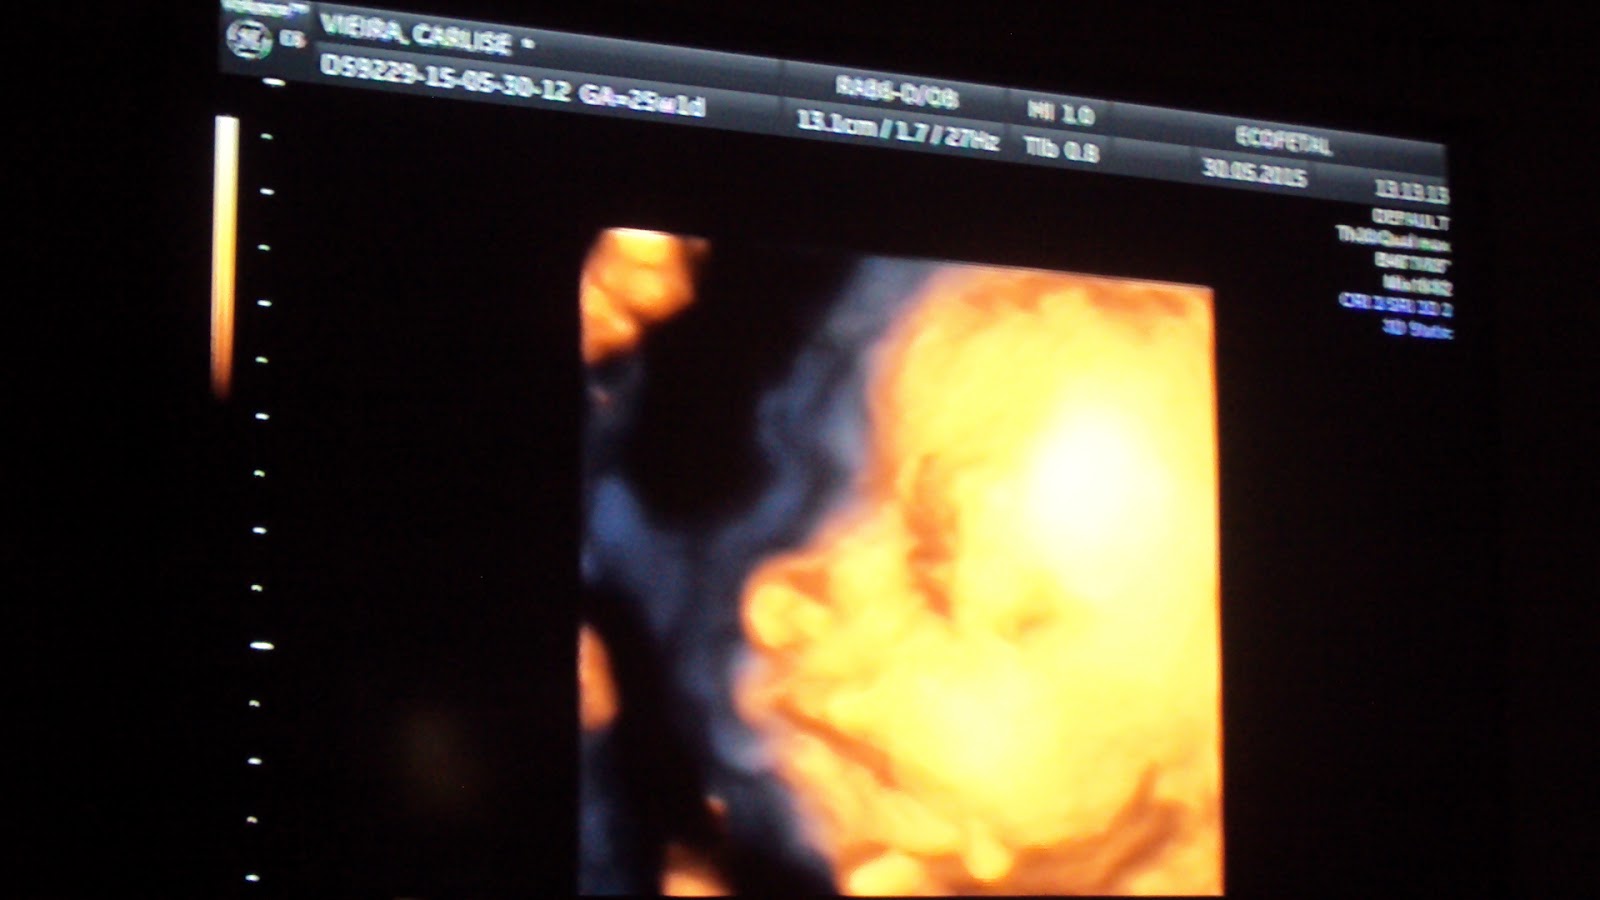

Hoje realizei a Ecografia 3D da Natália.

Os batimentos cardíacos da Natália estavam a 134 por minuto, está pesando 849 gramas e medindo 33 cm.

A Natália estava sentadinha e muito queridinha para realizar o exame.